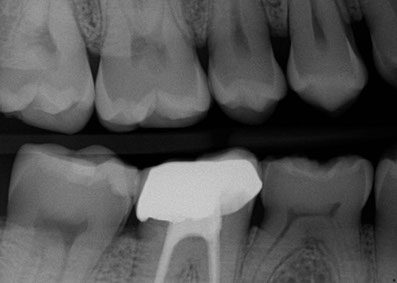

• Diagnostic X-rays